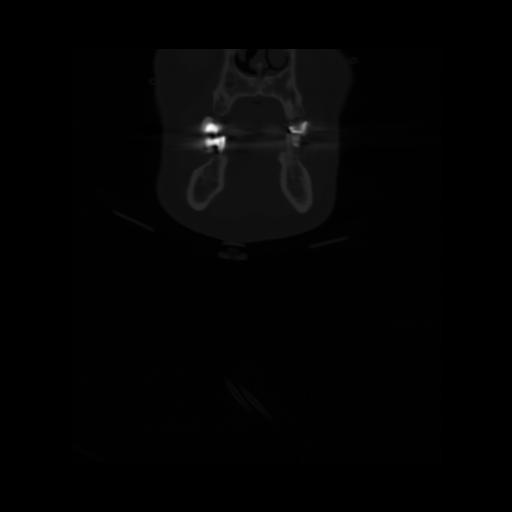

13 P.BLANDAS,,Coronal,2.000,P.BLANDAS,Coronal,